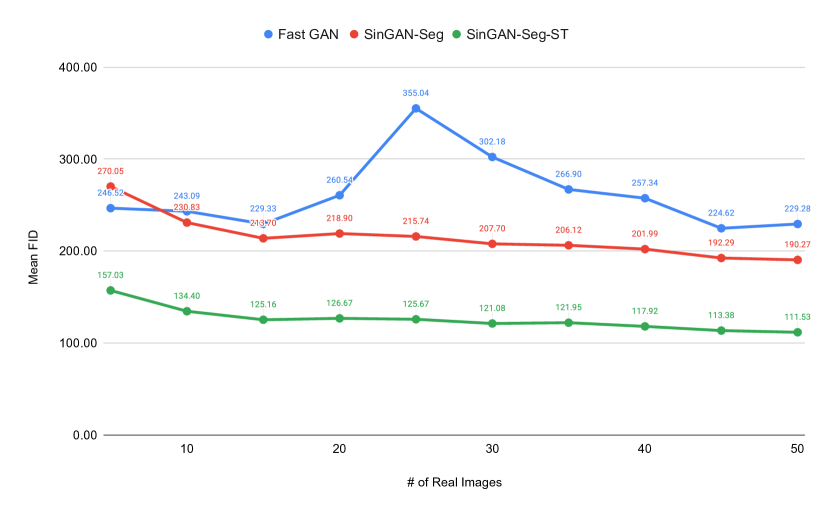

As FastGAN showed the best performance among all the other GANs, we decided to compare it with SinGAN-Seg and SinGAN-Seg-ST to evaluate generating synthetic data when training on datasets that contain few samples. We trained FastGAN architecture with a small number of images, such as , and generated the corresponding synthetic datasets, which have synthetic images from to . Then, we used the synthetic datasets to compare the performance with FastGAN trained on small datasets. FID values were calculated between the synthetic images and corresponding real images used to train the models. Mean and SD of FID values calculated from five synthetic datasets (Set 1, Set 2, Set 3, Set 4 and Set 5) generated from each GAN model are tabulated in Table 5. Moreover, mean FID values of FastGAN, SinGAN-Seg and SinGAN-Seg-ST are compared in Figure 13.

According the the table and the figure, it is clear that FastGAN is unstable with small training datasets while SinGAN-Seg and SinGAN-Seg-ST show good progress toward the number of images used to calculate FID values. SinGAN-Seg-ST is better than SinGAN-Seg as we experienced with previous experiments discussed in this study. It it worth to remind that SinGAN-Seg and SinGAN-Seg-ST does not depend on number of training images because it needs only a single image to train. Therefore, SinGAN-Seg model and it´s training pipeline used in this study prove the importance using it to generate synthetic datasets when GAN models do not have access to large training datasets.